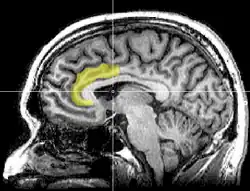

![]() Superficie medial del hemisferio cerebral izquierdo, con el cíngulo anterior resaltado. | ||

El córtex del cíngulo anterior (CCA) o circunvolución del cíngulo anterior es la parte frontal de la circunvolución del cíngulo, que parece un "collar" formado alrededor del cuerpo calloso, el mazo fibroso que transmite las señales neuronales entre los hemisferios cerebrales derecho e izquierdo. Consiste de las áreas de Brodmann 24, 32, y 33. Parece que juega un rol en una gama amplia de funciones autónomas, tales como regular la presión sanguínea y el ritmo cardíaco, como también para ciertas funciones cognitivas racionales, tales como la inhibición verbal, la anticipación de premio, la toma de decisiones, la empatía[1] y las emociones.[2][3]